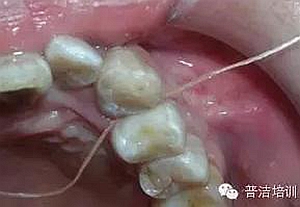

牙線去除鄰面樹(shù)脂粘結(jié)劑

鄰面拋光